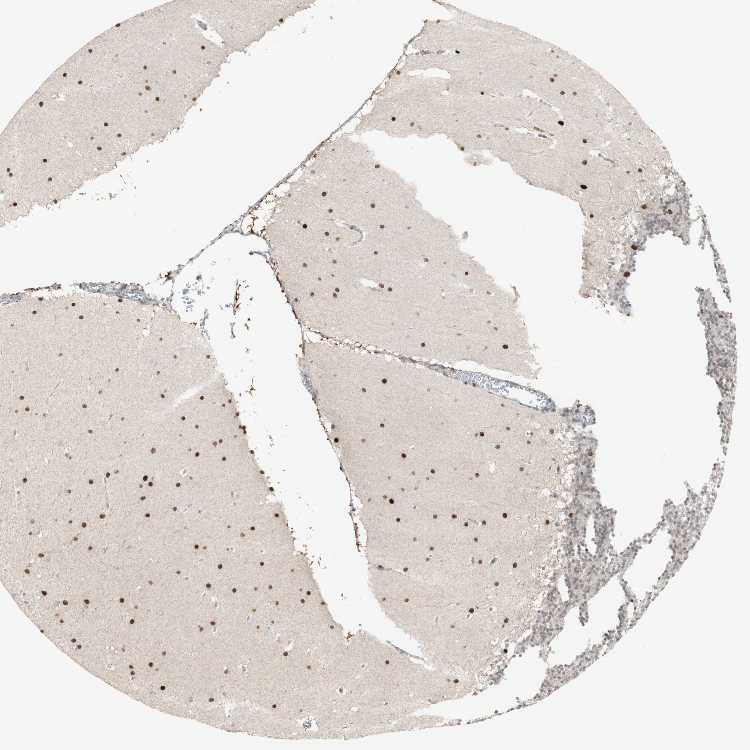

CEREBELLUM - Antibody stainingi

Antibody staining in the annotated cell types in the current human tissue is reported as not detected, low, medium, or high, based on conventional immunohistochemistry profiling in selected tissues. This score is based on the combination of the staining intensity and fraction of stained cells.

Each image is clickable and will lead to virtual microscopy that enables deeper exploration of all samples and also displays staining intensity scores, fraction scores and subcellular localization as well as patient and tissue information for each sample.

Antibody HPA011888Antibody HPA011889

Purkinje cells Not detectedHigh

Cells in granular layer Not detectedMedium

Cells in molecular layer Not detectedHigh